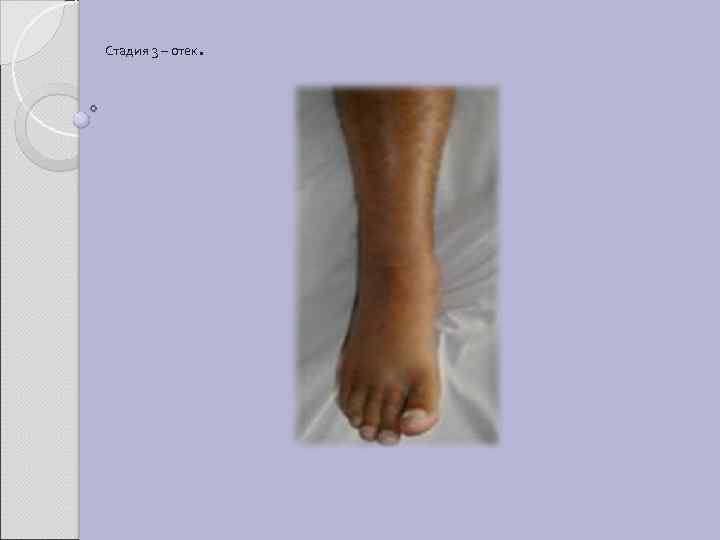

Стадия 3 – отек .